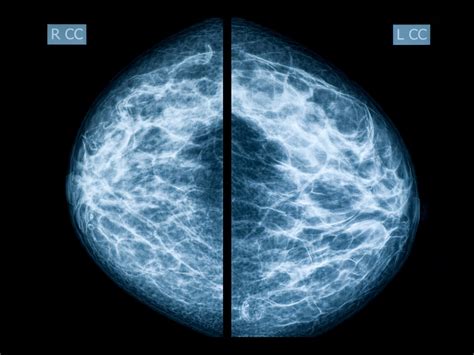

When a radiologist analyzes your scans, they are assessing the appearance of your breast tissue to ensure there are no signs of malignancy. Normal mammogram images typically display a balanced composition of fatty tissue, glandular tissue, and fibrous connective tissue. Because every woman’s breast density is unique, these images do not look identical for everyone; however, a "normal" result means the radiologist has not identified any suspicious masses, architectural distortions, or unusual clusters of microcalcifications that would necessitate further investigation.

Radiologists look for consistency and symmetry between the left and right breasts. While minor asymmetries are common, a significant change in the pattern of your tissue over time is what prompts a "call-back" for further testing. Essentially, normal results indicate that the internal anatomy of your breast appears healthy and consistent with your medical history and age-related tissue changes.

One of the most important factors influencing the appearance of your scan is breast density. Dense breast tissue contains more fibrous and glandular tissue compared to fatty tissue. On a mammogram, fatty tissue appears dark and transparent, while dense tissue appears white and opaque. This is why understanding density is vital when viewing normal mammogram images: